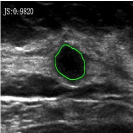

4.5 Comparison with breast ultrasound images segmentation

Unlike MR images mentioned above, ultrasound images offer real-time imaging but usually have lower resolution and contrast, making it difficult to differentiate between adjacent tissues and often introducing artifacts and noise that complicate segmentation. However, the RefLSM is robust to high levels of noise and intensity inhomogeneity, regardless of the type of medical image. To validate this, we perform segmentation comparison experiments on breast ultrasound images and calculate the Dice coefficient and Precision values for all models under evaluation.

In Fig. 10, the 1st row displays original images and initial contours for the RefLSM, while the second row shows the RefLSM’s segmentation results. Even with high levels of noise and severe intensity inhomogeneity caused by acoustic shadowing and motion artifacts, our model successfully identifies object edges, achieving an average Precision value of 0.9812. Table 4 shows that the RefLSM requires no more than 10 iterations and has an average processing time of only 1.79 seconds to segment images in Fig. 10.

To further validate the effectiveness of our model, we compared it with the ICTM, RESLS, and ALF models, represented in the 2nd, 3rd, and 4th rows of Fig. 11, respectively. The 5th row displays our proposed model. To better compare the segmentation results, we presented the initial contours in the 1st row, and the ground truth in the 6th row. We can observe that the ALF model struggles with boundary identification and has significant misclassification due to the boundary confusion in ultrasound images commonly caused by overlapping of soft tissues. While the ICTM and RESLS models perform well in some cases like column 1,4, and 7, they still face under-segmentation and over-segmentation problems when images are low contrast or have complex edges like column 1, 3 and 5. In addition to visual comparisons, we calculated the Precision and Dice coefficient for each model, as shown in Table 2. Clearly, the RefLSM outperforms all the other models in terms of mean score. Based on these results, we draw Fig. 12 to present the data distribution and facilitates comparison of different models’ performance across various breast ultrasound images. Although the ICTM model shows relatively close performance, it has nearly double the computational cost of the RefLSM. Therefore,the RefLSM demonstrates excellent segmentation capability and efficiency when processing ultrasound images.